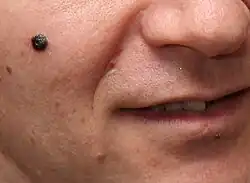

Os cancros da pele (português europeu) ou cânceres de pele (português brasileiro) são cancros que se formam na pele. São causados pelo desenvolvimento de células anormais que têm a capacidade de invadir ou de se espalhar para outras partes do corpo.[10] Existem três tipos principais: carcinoma basocelular (CBC), carcinoma de células escamosas (CCE) e melanoma.[1] O conjunto dos dois primeiros, e de uma série de cancros de pele menos comuns, é conhecido como "cancros de pele não melanoma" (CPNM).[5][11] O carcinoma basocelular é de crescimento lento e pode invadir os tecidos adjacentes, mas é pouco provável que se espalhe para regiões distantes ou que provoque a morte.[5] Muitas vezes aparece como uma área de pele elevada e indolor, que se pode apresentar brilhante e com pequenos vasos sanguíneos ou na forma de uma área de pele elevada com uma úlcera.[1] O carcinoma de células escamosas apresenta maior probabilidade de se espalhar.[5] Geralmente manifesta-se na forma de um pequeno inchaço com topo escamoso, embora possa também formar uma úlcera.[12] Os melanomas são os mais agressivos. Os sinais incluem a presença de um nevo melanocítico cujo tamanho, forma e cor se alterarm, que apresenta margens irregulares, que tem mais de uma cor, que provoca prurido ou que sangra.[3]

| Melanoma | A aparência comum é de uma área assimétrica, com bordas irregulares, variação de cor e frequentemente maior que 6 mm de diâmetro. Representa cerca de 5% dos casos de câncer de pele. A incidência tem aumentado cerca de 4 a 6% anualmente. É mais comum em mulheres entre 30 e 79 anos de idade e em indivíduos de cor branca. Quanto menor e menos espesso melhor as chances de cura.[22][23] |  |